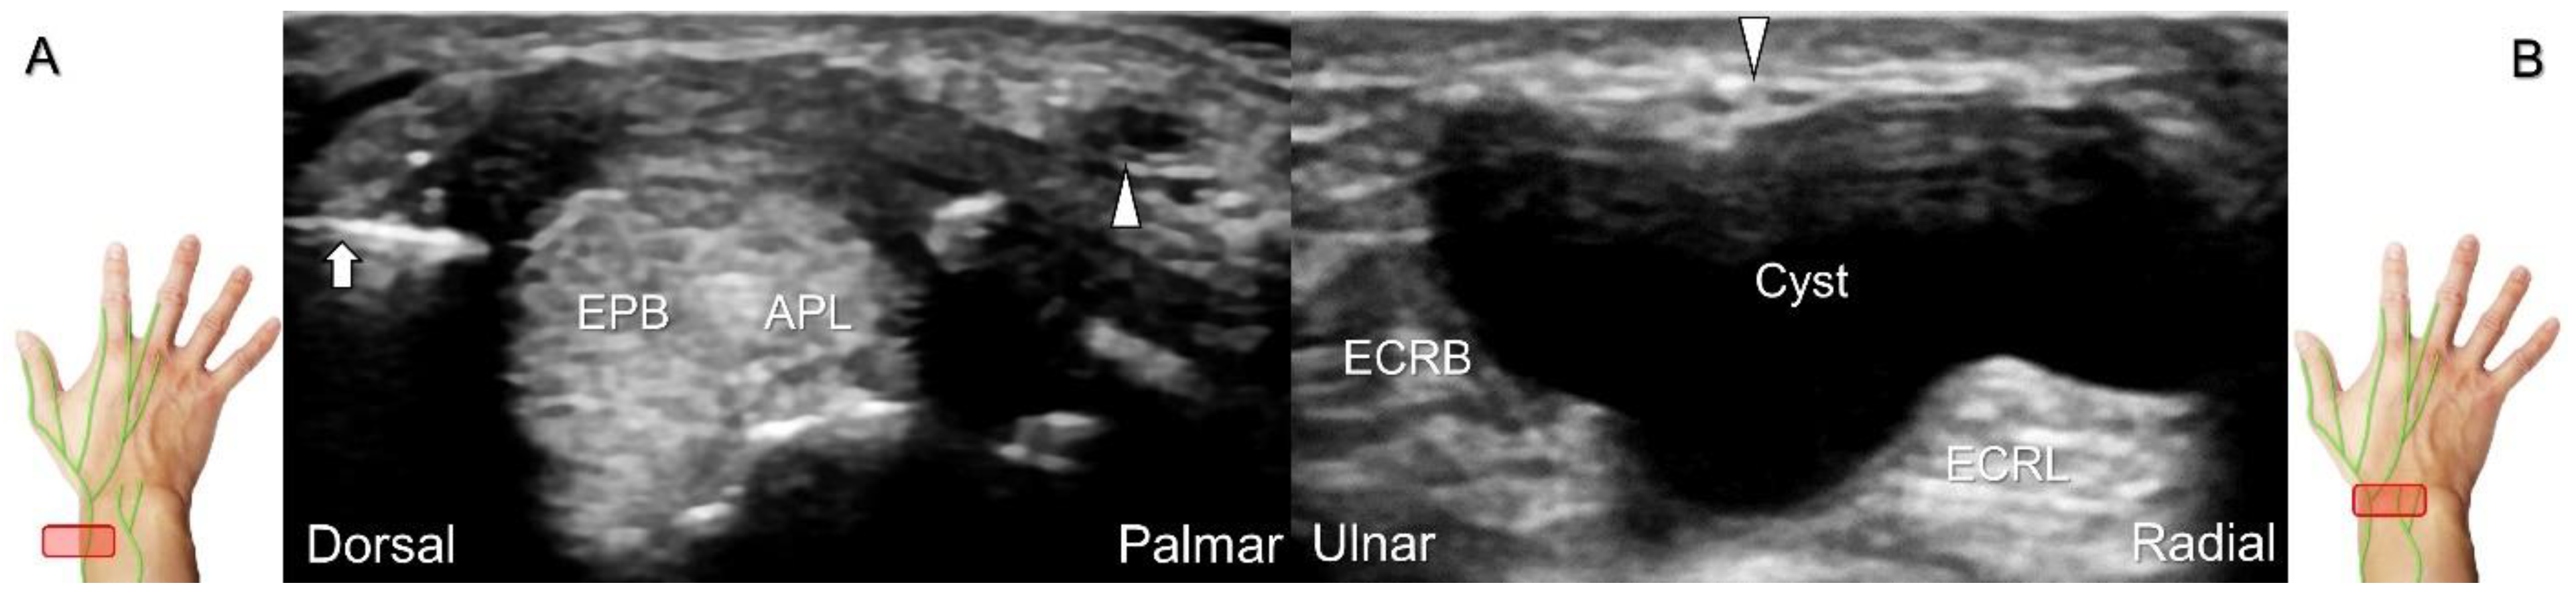

Cheiralgia paresthetica, also known as Wartenberg’s syndrome, is the compressive neuropathy of the superficial radial nerve. Symptoms such as tenderness, numbness, and allodynia can be exacerbated by wrist flexion and ulnar deviation. The nerve can be compressed by a handcuff, watch, bracelet, metal implant, ganglion cyst, or distal radius fracture. Nerve entrapment commonly takes place at the proximal intersection zone pertaining to the first and second extensor compartments (Figure 22).

Additionally, acupuncture and cannulation of the cephalic vein over the distal forearm can lead to nerve injury. To prevent iatrogenic injury, the superficial radial nerve before injection should also be recognized for de Quervain’s syndrome (Figure 23A) [44], ganglion cyst aspiration (Figure 23B), and catheterization (Figure 24A–C). For injection of the superficial radial nerve, an in-plane approach in the nerve’s short axis is preferred (Figure 24D).

Figure 23. Sonographic imaging of the superficial radial nerve beside the first extensor compartment of the wrist (A), and a ganglion cyst over the second extensor compartment of the wrist (B). White arrowheads: superficial radial nerve; white arrow: needle. APL: abductor pollicis longus tendon; EPB: extensor pollicis brevis tendon; ECRL: extensor carpi radialis longus tendon; ECRB: extensor carpi radialis brevis tendon.